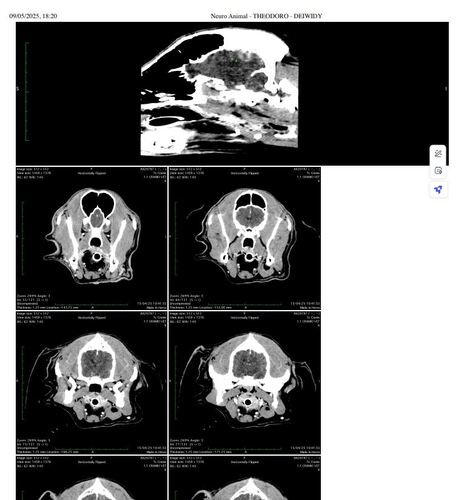

Agora é sua vez de me ajudar, a pouco tempo descobrimos um tumor cerebral operável, estou tendo muitas convulsões e não consigo me equilibrar e enxergar direito por causa do tumor. nesse último ano o meu dono lutou com todas as forças para sempre me manter saudável, fizemos cirurgia de catarata, tiramos um tumor no baço, infelizmente esse tratamento é muito caro pois ele nem acabou de pagar a cirurgia no meu olho pra enxergar bem. meu corpo ainda esta saudável querendo que eu permaneça aqui mais um pouco para dar alegria e amor porém esse tumor esta sendo um grande empecilho e preciso operar o quanto antes venho pedir a ajuda de vocês pra juntos tentarmos tirar ele e me fazer ficar mais um pouco aqui nesse plano!

algumas fotos minhas novinho trabalhando e até o dia de hoje e também o exame mostrando o tumor.